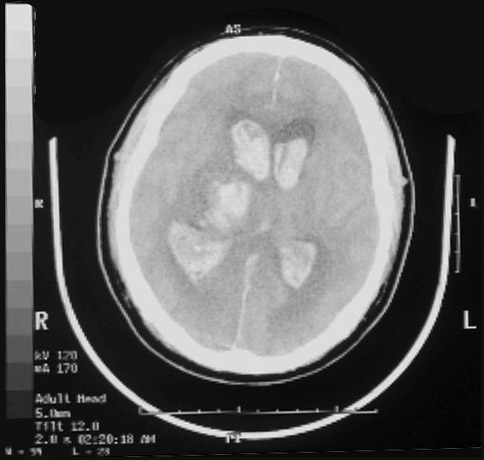

Click on the right thalamic hemorrhage in the radiograph below:

This is a computed tomographic (CT) scan demonstrating a hypertensive hemorrhage in the right thalamus that has extended into the ventricular system. Hemorrhages in this location are not amenable to surgical intervention with removal of the blood.